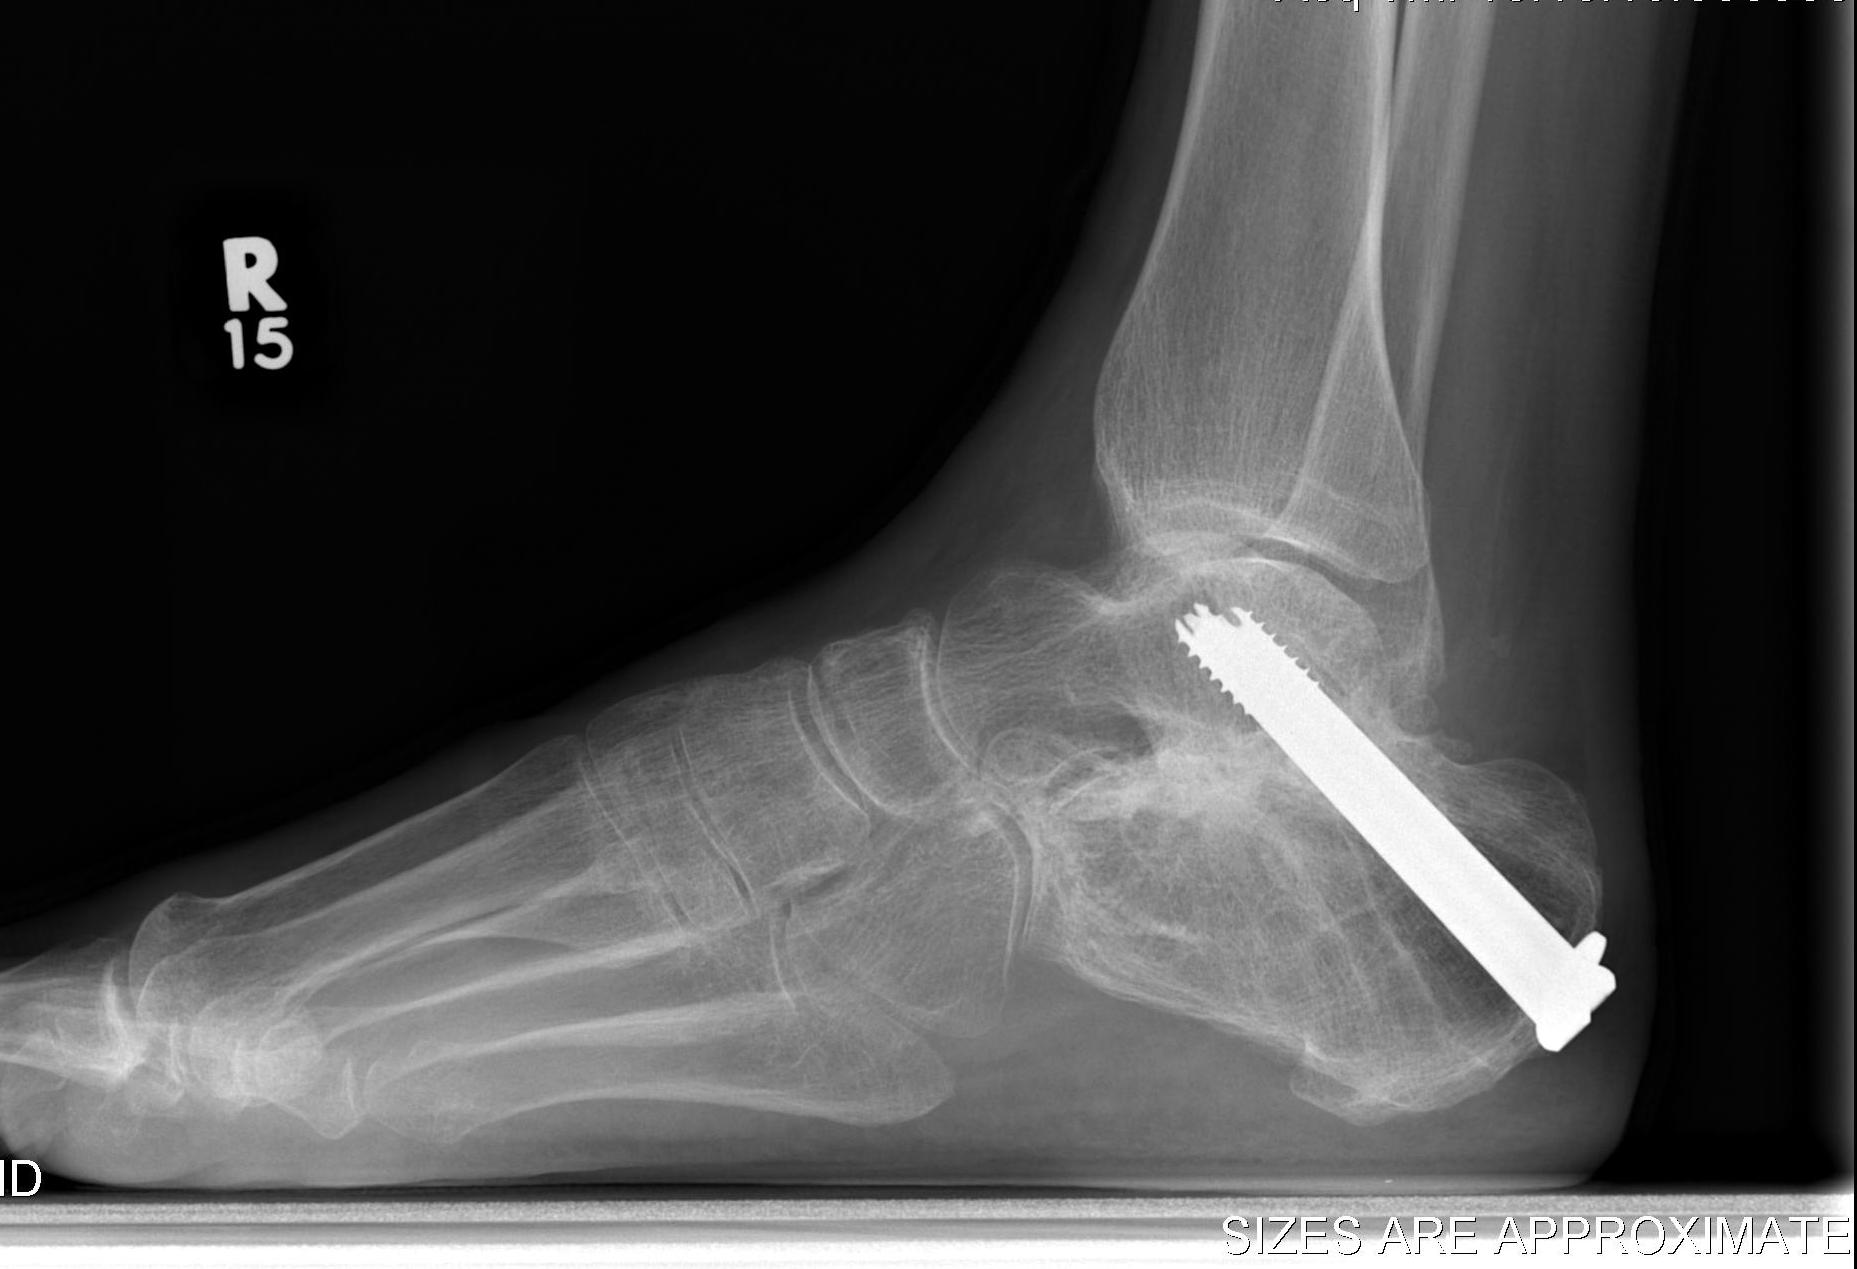

Fixation

- 6.5 mm/ 8.0 mm cannulated screw

- inferior calcaneum into body and neck of talus / talus to calcaneum